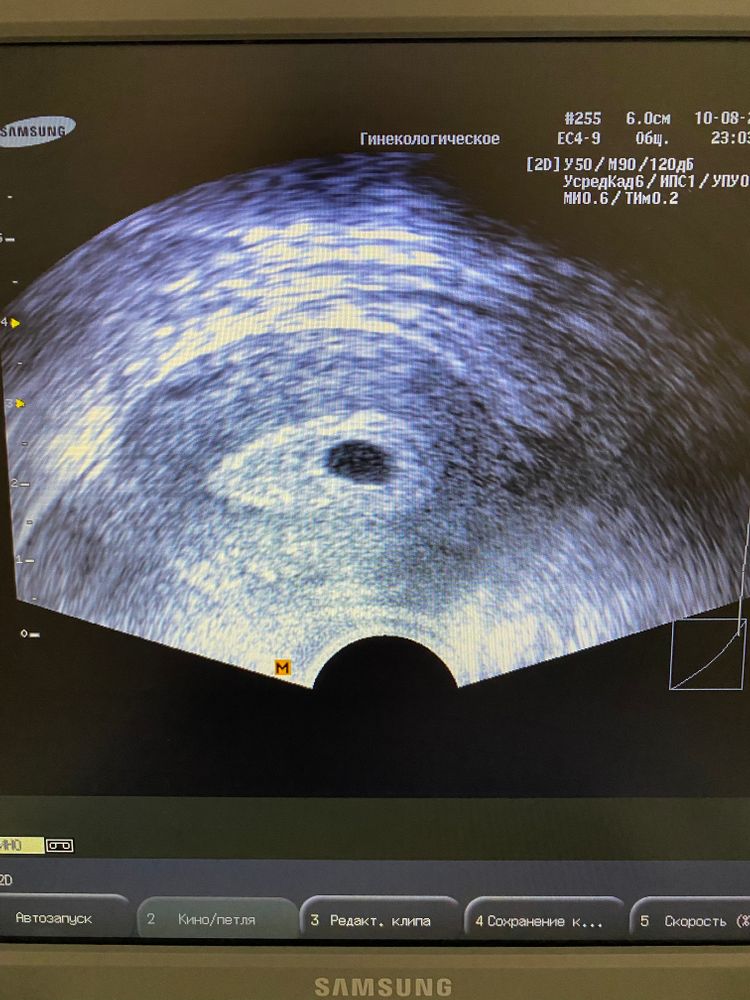

Вчера было первое УЗИ у репродуктолога на 21 дпп. Беременность подтвердили! 🥳 Все хорошо, плодное яйцо хорошего размера, желточный мешочек она тоже увидела. И вот вопрос: ре назначила экспертное узи на 35 дпп. Зачем на таком маленьком сроке экспертное узи за 4000 у них в клинике? А так же назначила провести исследование тромбодинамики для того, чтобы понять можно ли отменять Флюксум(аналог клексана), тоже у них в клинике за 5600. Это выкачка денег, или действительно нужные обследования?

На 21 дпп подтвердили беременность, а на 35 сердцебиение,так и должно быть, нужно же понять есть сердцебиение или нет, странно что вы это всё не уточнили у врача. Когда колишь кроворазжижающие каждые 2 недели нужно проверять тромбодинамику. Я отправляла анализы в ватсапп гематологу и она смотрела, бесплатно. А если консультация, то нужно платить. Получается платишь и за анализ и за консультацию. Удовольствие конечно не дешевое, но тромбодинамику нужно обязательно держать под контролем.

Я по ОМС делала, и в клинике предусматривается два бесплатных УЗИ. Делала на 19 и 29 дпп, причём просто глянул если ли эмбрион и сб. На таком сроке экспертное не понятно зачем, тут главное увидеть развивающую Б, а скрининговое делается уже после 11 недели

Я тоже на квадропарине, мониторю кровь каждые 2-3 недели для гематолога, сдаю в инвитро. Там дешевле, чем в клинике где я наблюдаюсь. Узи нужно, чтоб увидеть эмбрион. Но я делала УЗИ при беременности раннего срока (до 11 недель). Это 1700. А скрининг тут стоит не мало 7700 🙈. Просто непонятно, зачем вам скрининг на 35 дпп 🤦🏻♀️. Его с 12 недель обычно делают.

На 35 дпп должны увидеть эмбрион и услышать сердцебиение. Тромбодинамику каждые 2 недели нужно мониторить, чтобы понимать нужен еще клексан или уже отменять или наоборот увеличить дозировку. Если не устраивает ценник, конечно же можно сдать анализы в другом месте, и узи там, где вам удобно. Мне тоже назначали контроль ТД, когда наступит беременность (еще переноса не было). А узи по усмотрению, где хочу. Мой репродуктолог никогда не настаивает.